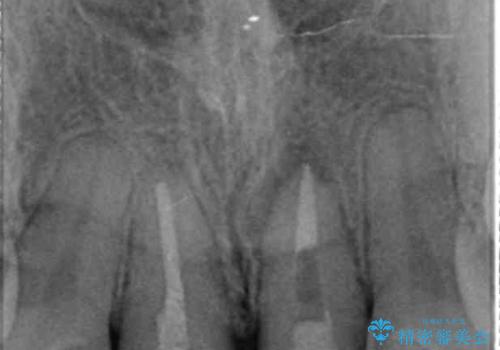

- 「幼少期に転んで治療した前歯がうずく、疲れると膿が出る。」と治療を希望され来院されました。

X線写真検査に加え圧痛、打診痛が認められたため、慢性根尖性歯周炎と診断し、根管治療から行うセラミック治療を計画します。